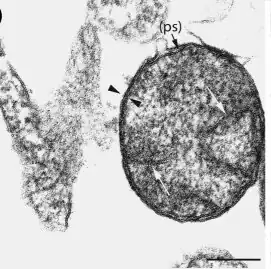

.jpg.webp)